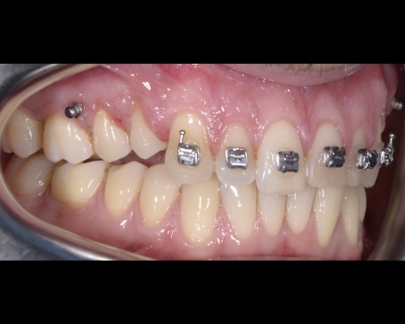

Sunt benzi elastice mici, din latex, folosite pentru corectarea mușcăturii și intercuspidarea dinților.

Elasticele se atașează de brackeții dinților superiori, respectiv inferiori și vin în diferite dimensiuni și grade de forță.

![]() | ![]() |

Elasticele ortodontice corectează raportul dintre maxilar și mandibulă (mușcătura). Sunt purtate conform indicațiilor medicului și sunt esențiale în multe tratamente pentru alinierea corectă a arcadelor.